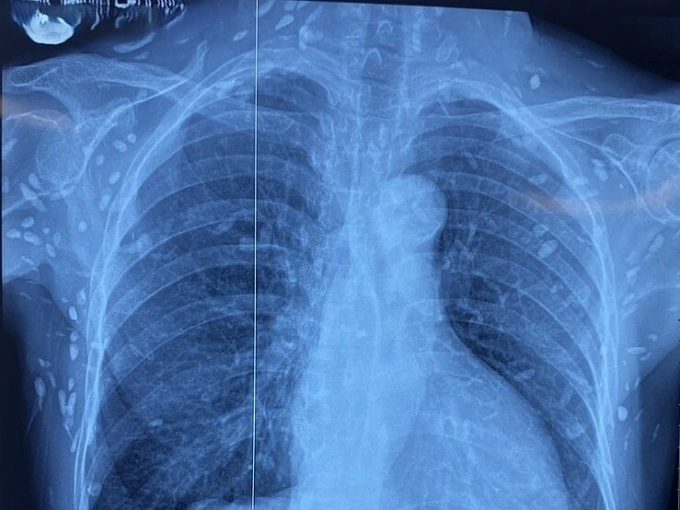

Bà được chuyển lên từ cơ sở y tế tuyến dưới đến Bệnh viện Trung ương Quân đội 108 vì rối loạn ý thức đe dọa suy hô hấp. Hình ảnh cắt lớp vi tính sọ não và X-quang ngực cho thấy rất nhiều nốt cản quang trong nhu mô não và dưới da vùng ngực - bụng. Một vài u cục với kích thước tương ứng có thể sờ thấy dưới da vùng ngực và cánh tay của người bệnh.

ThS.BS Nguyễn Sỹ Thấu, khoa Hồi sức Truyền nhiễm, cho hay xét nghiệm kháng thể IgM âm tính với sán dây lợn, song các tổn thương trên X-quang cho thấy có thể người bệnh trước đây bị nhiễm ấu trùng sán dây lợn, sau đó các nang sán trở nên vôi hóa và tồn tại lâu dài trong tổ chức. Người bệnh được điều trị theo phác đồ, ra viện tiếp tục điều trị theo tuyến.

Phim chụp cho thấy nhiều nang sán tại thành ngực-bụng và chi trên bệnh nhân. Ảnh: Bệnh viện cung cấp

"Nang sán dây lợn có thể tự thoái hóa hoặc bị vôi hóa, tạo nên hình ảnh cản quang phát hiện được trên phim X-quang như bệnh nhân trên", bác sĩ Thấu nói.